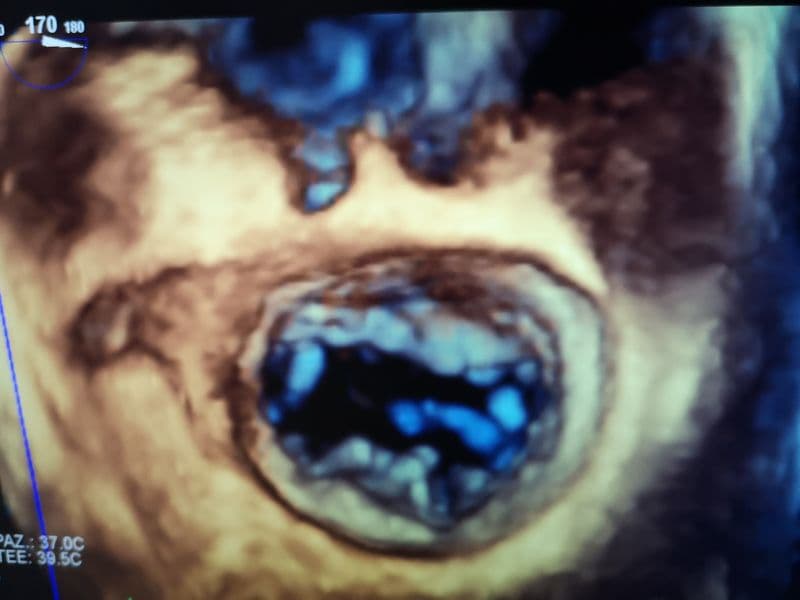

Sono importanti per la cura e trattamento delle malattie cardiovascolari. La possibilità di ottenere immagini a elevata risoluzione con ricostruzione tridimensionale consente, infatti, di inquadrare la patologia valvolare e di definirne la corretta indicazione chirurgica nell’ottica della riparazione e non della sostituzione delle valvole cardiache. L'ecocardiografia tridimensionale consente, inoltre, l'inquadramento della patologia strutturale (per esempio della valvola mitralica, della valvola aortica, del setto interatriale) e il monitoraggio delle procedure interventistiche mininvasive. I nuovi ecocardiografi dispongono anche di un software che permette una diagnosi precoce in caso di sospetta cardiotossicità da chemioterapici e/o da radioterapia.